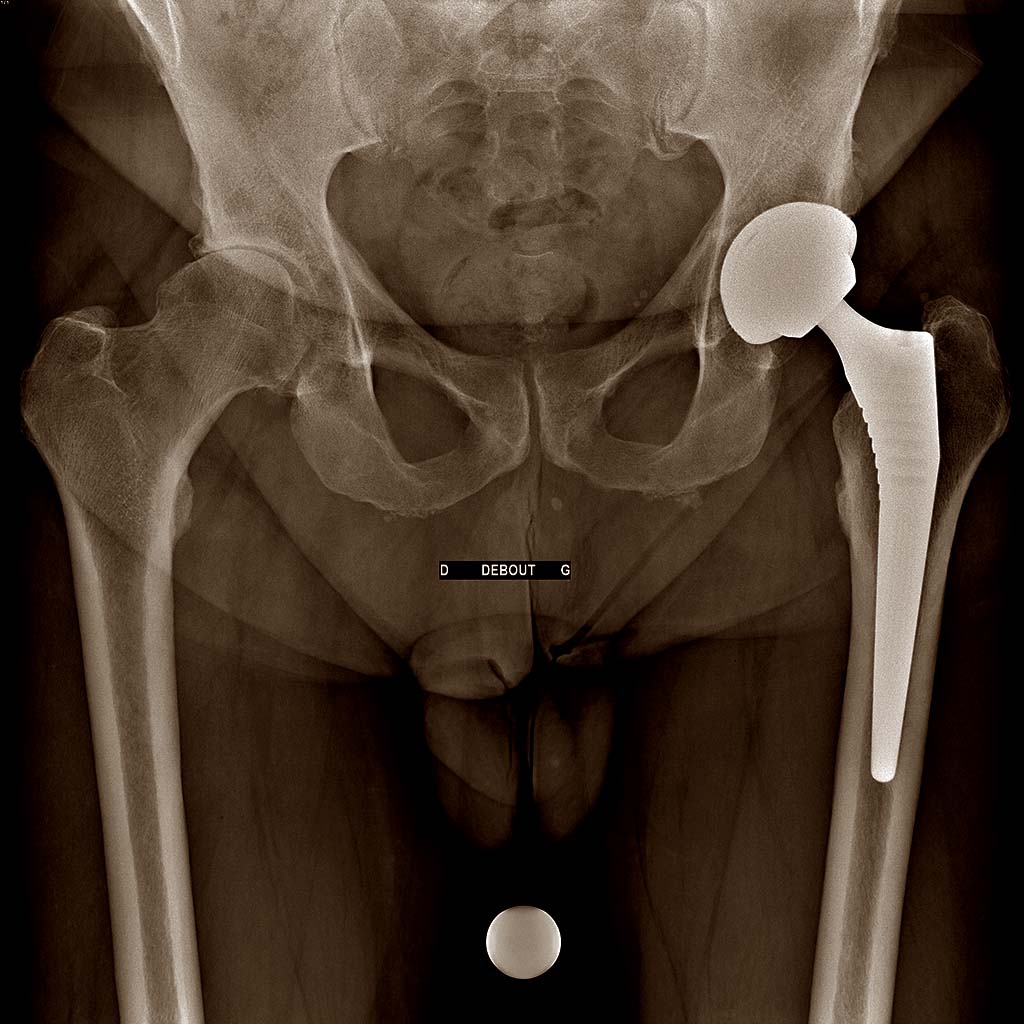

Aponévrosite Plantaire

Aponévrosite Plantaire...

Lire la suite →